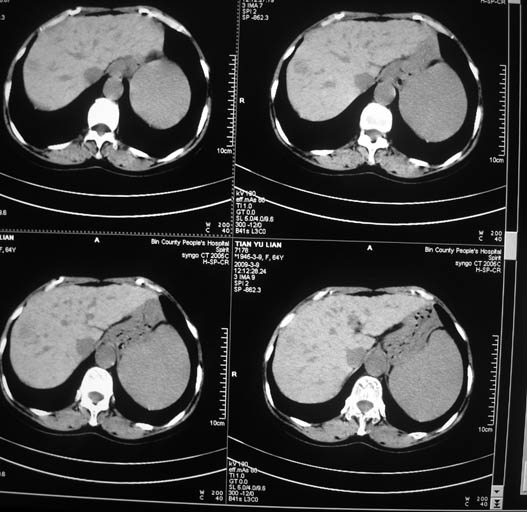

标题: CT18578:女,64岁,腹痛。 [打印本页]

标题: CT18578:女,64岁,腹痛。

女,64岁,腹痛。彩超示肝占位。

肝硬化肝癌,瘤栓?肝总管扩张。

1)肝右叶占位性病变,性质待定(不排除巨块型肝癌可能);建议行进一步检查。2)胆囊炎。3)脾大。

1.肝脏形态不太规整,肝内胆管扩张,考虑有肝硬化,建议问病史。

2.肝右叶占位性病变,肝癌可能性大。

3.脾脏增大。

1.肝硬化

2.肝右叶占位性病变,肝癌可能性大,建议ct增强

3.脾脏增大

肝硬化肝癌,门脉右支瘤栓肝总管扩张